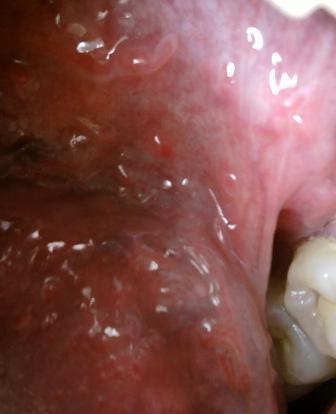

石家庄九州皮肤病医院 > 尖锐湿疣 > > > 尖锐湿疣对人体健康有怎样的危害纵观尖锐湿疣的治疗方法,传统的单一疗法并不能达到理想的治疗效果,对于尖锐湿疣这种顽固性疾病的治疗,最好是应该坚持综合治疗的方法。尖锐湿疣的危害是比较大的,对于人们身心健康带来双重危害。

尖锐湿疣对人体健康有怎样的危害尖锐湿疣病毒传染性是比较强的,所以在危害自身健康的同时还会危害他人,害人害已。尖锐湿疣属于性病的范畴,一旦确诊患病,很多人会背上沉重的心里负担。内心的担忧,害怕,沮丧会导致很多人讳疾忌医。在早期都是治疗的关键时期,患者一定要做好尖锐湿疣的护理与保健,以使自己彻底摆脱尖锐湿疣的困扰。尖锐湿疣久治不愈会诱发炎症,生殖器癌变,影响人们正常生育系统。尖锐湿疣多发于年轻的男女,20岁到25岁是疾病的高发期。而生殖器癌多见于年长的人。